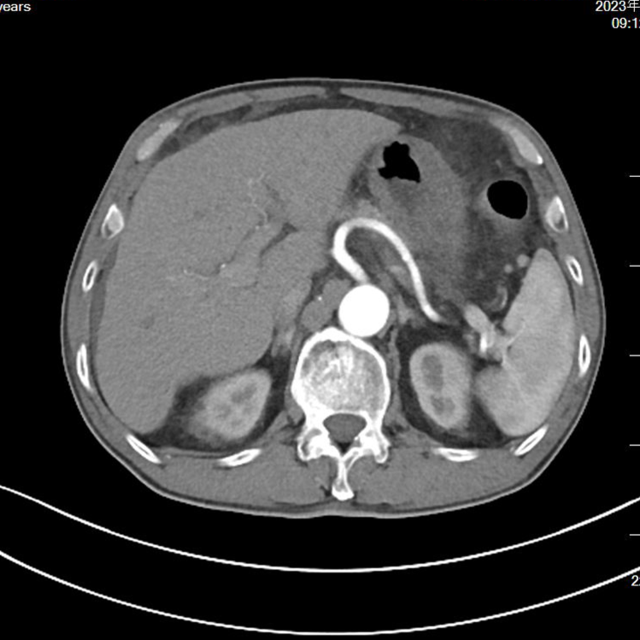

▲新辅助治疗后